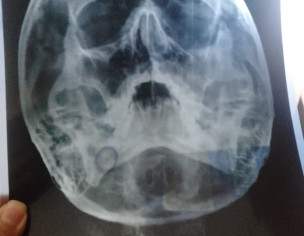

mera 7 din phly accident hua tha or meri nakk sy bohat bleeding hoi or osi din sy meri ankh k nechy jo hadii wo thori tot gi hy my apna pori trha moh ni khol skta ab na kuch kha paa rha hu mayoo hospital walo ny mjy operation ka kaha hy k ap operation krwa lo mey yeh pochna tha k yeh chez bina operate hove thk ni hoskti kya or agr operate he hona hhy to wo kis trha hoga mtlb k cuts lgygy face kya orr hadii face ke kesyy shi hogi please esky bary my mjy guide krdy

Aoa,apko left ZMC (Mid face) fracture hai.Ye baghair operation theek nai Hoga.You should follow what Mayo hospital surgeons have said

Attach Photo here: